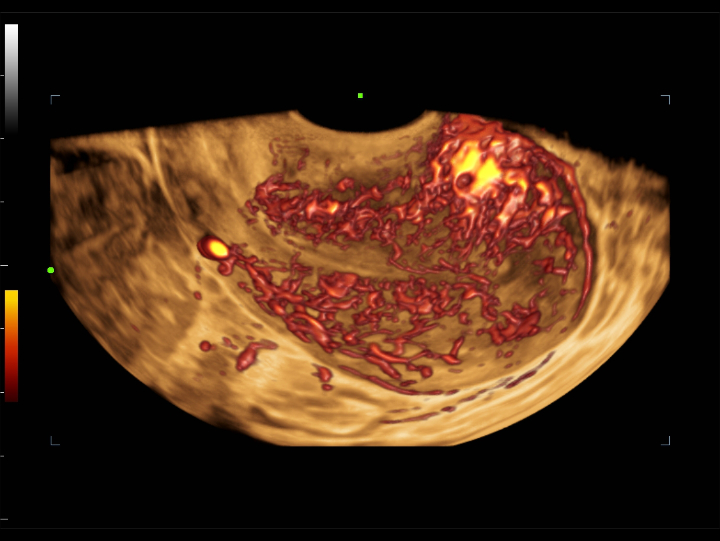

UWN+ CEUS provides excellence contrast agent sensitivity and image penetration to get more diagnosis information for gynecology tumor or other difficult diseases. Also MindrayŌĆÖs STE (Sound Trouch Elastogtaphy) can quantitatively evaluate tissue stiffness which is helpful for previse diagnosis of difficult uterus, cervix and ovary diseases.